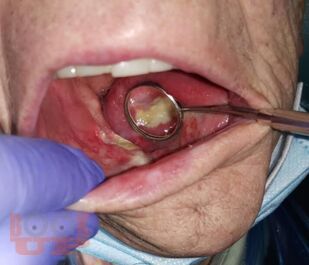

Остеонекроз челюсти

Журавлев А. Н. Остеонекроз челюсти : Учебно-методическое пособие для ординаторов специальностей 31.08.74 Стоматология хирургическая, 31.08.69 Челюстно-лицевая хирургия / А. Н. Журавлев, Л. Б. Филимонова, А. А. Кабанова. - Рязань : РязГМУ, 2024. - 56 c. - Текст : электронный // ЭБС "Букап" : [сайт]. - URL : https://www.books-up.ru/ru/book/osteonekroz-chelyusti-17719937/ (дата обращения: 16.03.2026). - Режим доступа : по подписке.

Настоящее учебно-методическое пособие составлено в соответствии с программой ФГОС ВО, предназначено для ординаторов специальностей 31.08.74 Стоматология хирургическая и 31.08.69 Челюстно-лицевая хирургия.